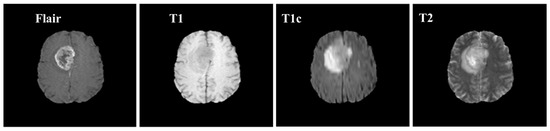

Brain MRI tumors have complicated structures and shapes, which makes the tumor classification and segmentation process more difficult using uni-modality. MRI machines provide an option to capture multimodality images with a more detailed representation of brain tissues [9]. During the MRI scan of a patient, the MRI machine produces different types of MRI sequences including T1, T2, T1c, and Flair, which are based on the Time to Echo (TE), Repetition Time (TR), brightness and contrast values. Figure 3 describes the four different brain MRI modalities and Figure 4 describes the three different types of healthy tissues inside the brain.

Samples of these four modalities (T1, T2, T1c, Flair) are presented in Figure 6. All four modalities have 620 MR images which make a total of 239,320 MR images for all 384 cases and a total of 169,880 MR images 274 train images as shown in Table 2. In BraTS dataset, labels are provided only for the train images so only train images are used for experiments. The dataset is divided into 60% for training, 20% for validation and 20% for the testing. BraTS provides data in MetaImage (.mha) format which is used to store 3D medical images. For each modality of every case, there are 155 slices with 240 × 240 pixel dimensions which are stored in a single mha file.

Figure 3. Pictorial view of brain MR Image modalities.